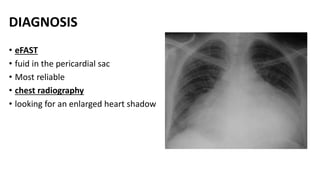

DIAGNOSIS

• eFAST

• fuid in the pericardial sac

• Most reliable

• chest radiography

• looking for an enlarged heart shadow